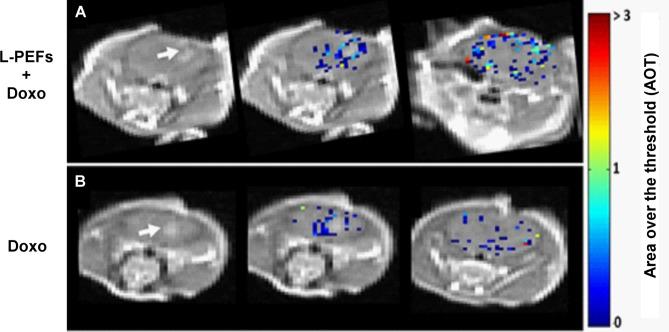

L-PEFs were applied using plate electrodes placed on the intact skull of naïve mice. L-PEFs/Sham mice were scanned immediately after the procedure by DCM ("MRI experiment"), or injected with Doxo and Trypan blue followed by delayed (4 h) perfusion and brain extraction ("Doxo experiment"). Doxo concentrations were measured in brain samples using confocal microscopy and compared to IC of Doxo in glioma cell lines in vitro. In order to map BBBo extent throughout the brain, pixel by pixel MR image analysis was performed using the DCM data. Finally, the efficacy of L-PEFs in combination with Doxo was tested in nude mice bearing intracranial human glioma tumors.

Significant amount of Doxo was found in cortical regions of all L-PEFs-treated mice brains (0.50 ± 0.06 µg Doxo/gr brain) while in Sham brains, Doxo concentrations were below or on the verge of detection limit (0.03 ± 0.02 µg Doxo/gr brain). This concentration was x97 higher than IC of Doxo calculated in gl261 mouse glioma cells and x8 higher than IC of Doxo calculated in U87 human glioma cells. DCM analysis revealed significant BBBo levels in the cortical regions of L-PEFs-treated mice; the average volume of BBBo in the L-PEFs-treated mice was x29 higher than in the Sham group. The calculated BBBo levels dropped exponentially as a function of BBBo threshold, similarly to the electric fields distribution in the brain. Finally, combining non-invasive L-PEFs with Doxo significantly decreased brain tumors growth rates in nude mice.

Our results demonstrate significant BBBo levels induced by extra-cranial L-PEFs, enabling efficient delivery of therapeutic Doxo doses into the brain and reducing tumor growth. As BBBo was undetectable by standard contrast-enhanced MRI, DCM was applied to generate maps depicting the BBBo levels throughout the brain. These findings suggest that BDF is a promising technology for efficient drug delivery into the brain with important implications for future treatment of brain cancer and additional CNS diseases.

在所有接受 L-PEF 治疗的小鼠大脑的皮质区域都发现了大量的 Doxo(0.50 ± 0.06μg Doxo/gr 脑),而在 Sham 大脑中,Doxo 浓度低于或接近检测限(0.03 ± 0.02μg Doxo/gr 脑)。这一浓度是在 Gl261 小鼠神经胶质瘤细胞中计算出的 Doxo 的 IC 的 x97 倍,是在 U87 人神经胶质瘤细胞中计算出的 Doxo 的 IC 的 x8 倍。DCM 分析显示,在接受 L-PEF 治疗的小鼠皮质区域存在显著的 BBBo 水平;接受 L-PEF 治疗的小鼠的平均 BBBo 体积比 Sham 组高 x29。计算出的 BBBo 水平随着 BBBo 阈值的指数下降,类似于大脑中电场的分布。最后,将非侵入性的 L-PEF 与 Doxo 联合使用,显著降低了裸鼠脑肿瘤的生长速度。

我们的结果表明,颅外 L-PEF 诱导了显著的 BBBo 水平,使治疗剂量的 Doxo 能够有效地递送到大脑,并减少肿瘤的生长。由于标准的对比增强 MRI 无法检测到 BBBo,因此应用了 DCM 来生成描绘大脑中 BBBo 水平的图谱。这些发现表明,BDF 是一种有前途的高效药物输送技术,对未来治疗脑癌和其他 CNS 疾病具有重要意义。